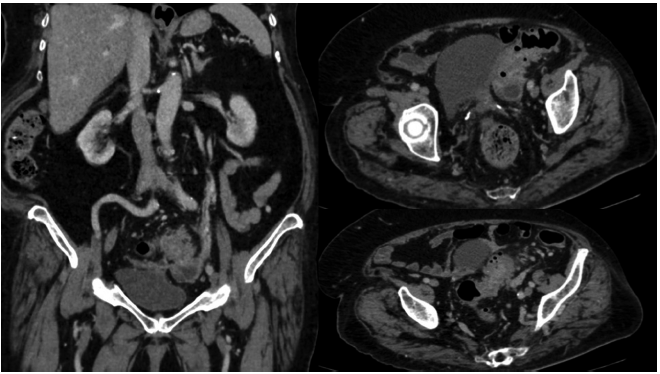

En el grupo de tomografía con contraste oral que requirieron de manejo quirúrgico, solo se encontraron verdaderos positivos (Figura 1).

De forma similar, en el grupo con tomografía sin contraste oral, que requirieron manejo quirúrgico (14 pacientes), no se encontraron resultados falsos negativos ni verdaderos negativos. En 13 de ellos la tomografía coincidió con el diagnóstico final. En un paciente la tomografía reportó diverticulitis con diagnóstico final de tumor en el sigmoides perforado sin diverticulitis, lo cual constituye un falso positivo.